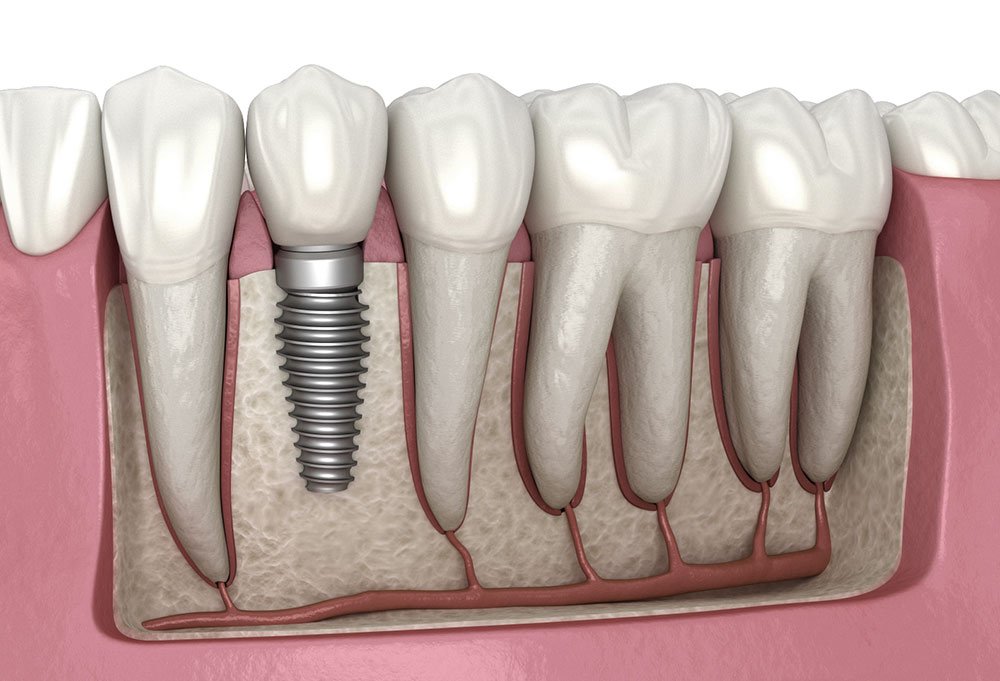

Dental implants are a modern, permanent solution for missing teeth. At our clinic, we use high-quality titanium implants that act as artificial roots, surgically placed into the jawbone. Over 2–3 months, the implant integrates with the bone through a process called osseointegration, providing a stable foundation for a crown, bridge, or denture. Implants look, feel, and function like natural teeth, allowing you to eat, speak, and smile confidently. They also help preserve jawbone density and facial structure, unlike traditional dentures. The procedure is carefully planned using digital imaging and performed under local anesthesia for minimal discomfort. Dr. Anuradha’s expertise ensures high success rates and precise outcomes. Whether replacing a single tooth or multiple teeth, dental implants restore aesthetics and function while offering long-term durability. Our clinic maintains strict hygiene and sterilization protocols, ensuring each implant procedure is safe, effective, and customized to your unique oral health needs.